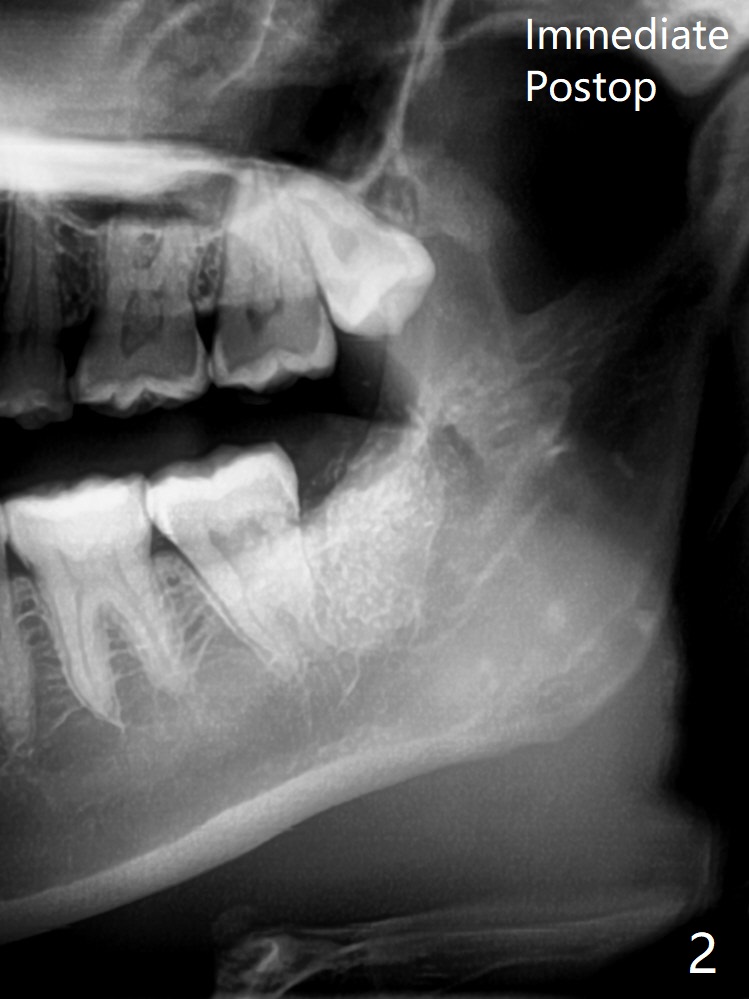

29岁(越过最佳骨再生年龄)女要求拔除左下8,它与7之间骨质非常薄(图一),拔除后需要比较好,便利的植骨材料:医用石膏(Bond Apatite,图二),表面放置1/2胶原塞,4-0 PGA缝合。术后两个月回来拔除左上8(“刺激颊粘膜”,其实远中牙龈红肿),临床上左下8近中颊侧仍有一个小开口,石膏与骨质界限开始不清楚了(图三)。